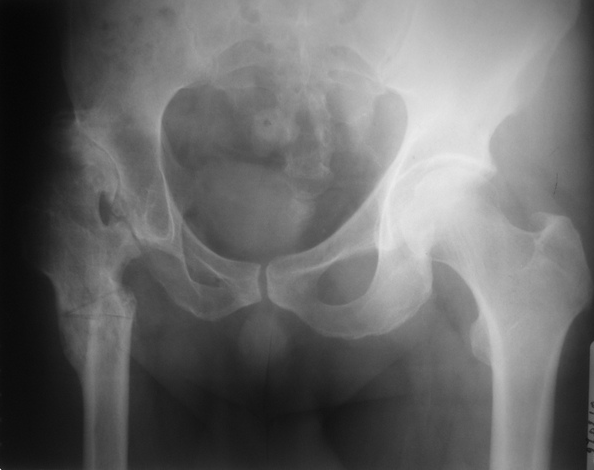

Выполнена одномоментная коррекция деформации, эндопротезирование DePyu Pinnacle-AML.Пластинка с деротационной целью. При использовании ножки с прямоугольным сечением, думаю можно и без нее